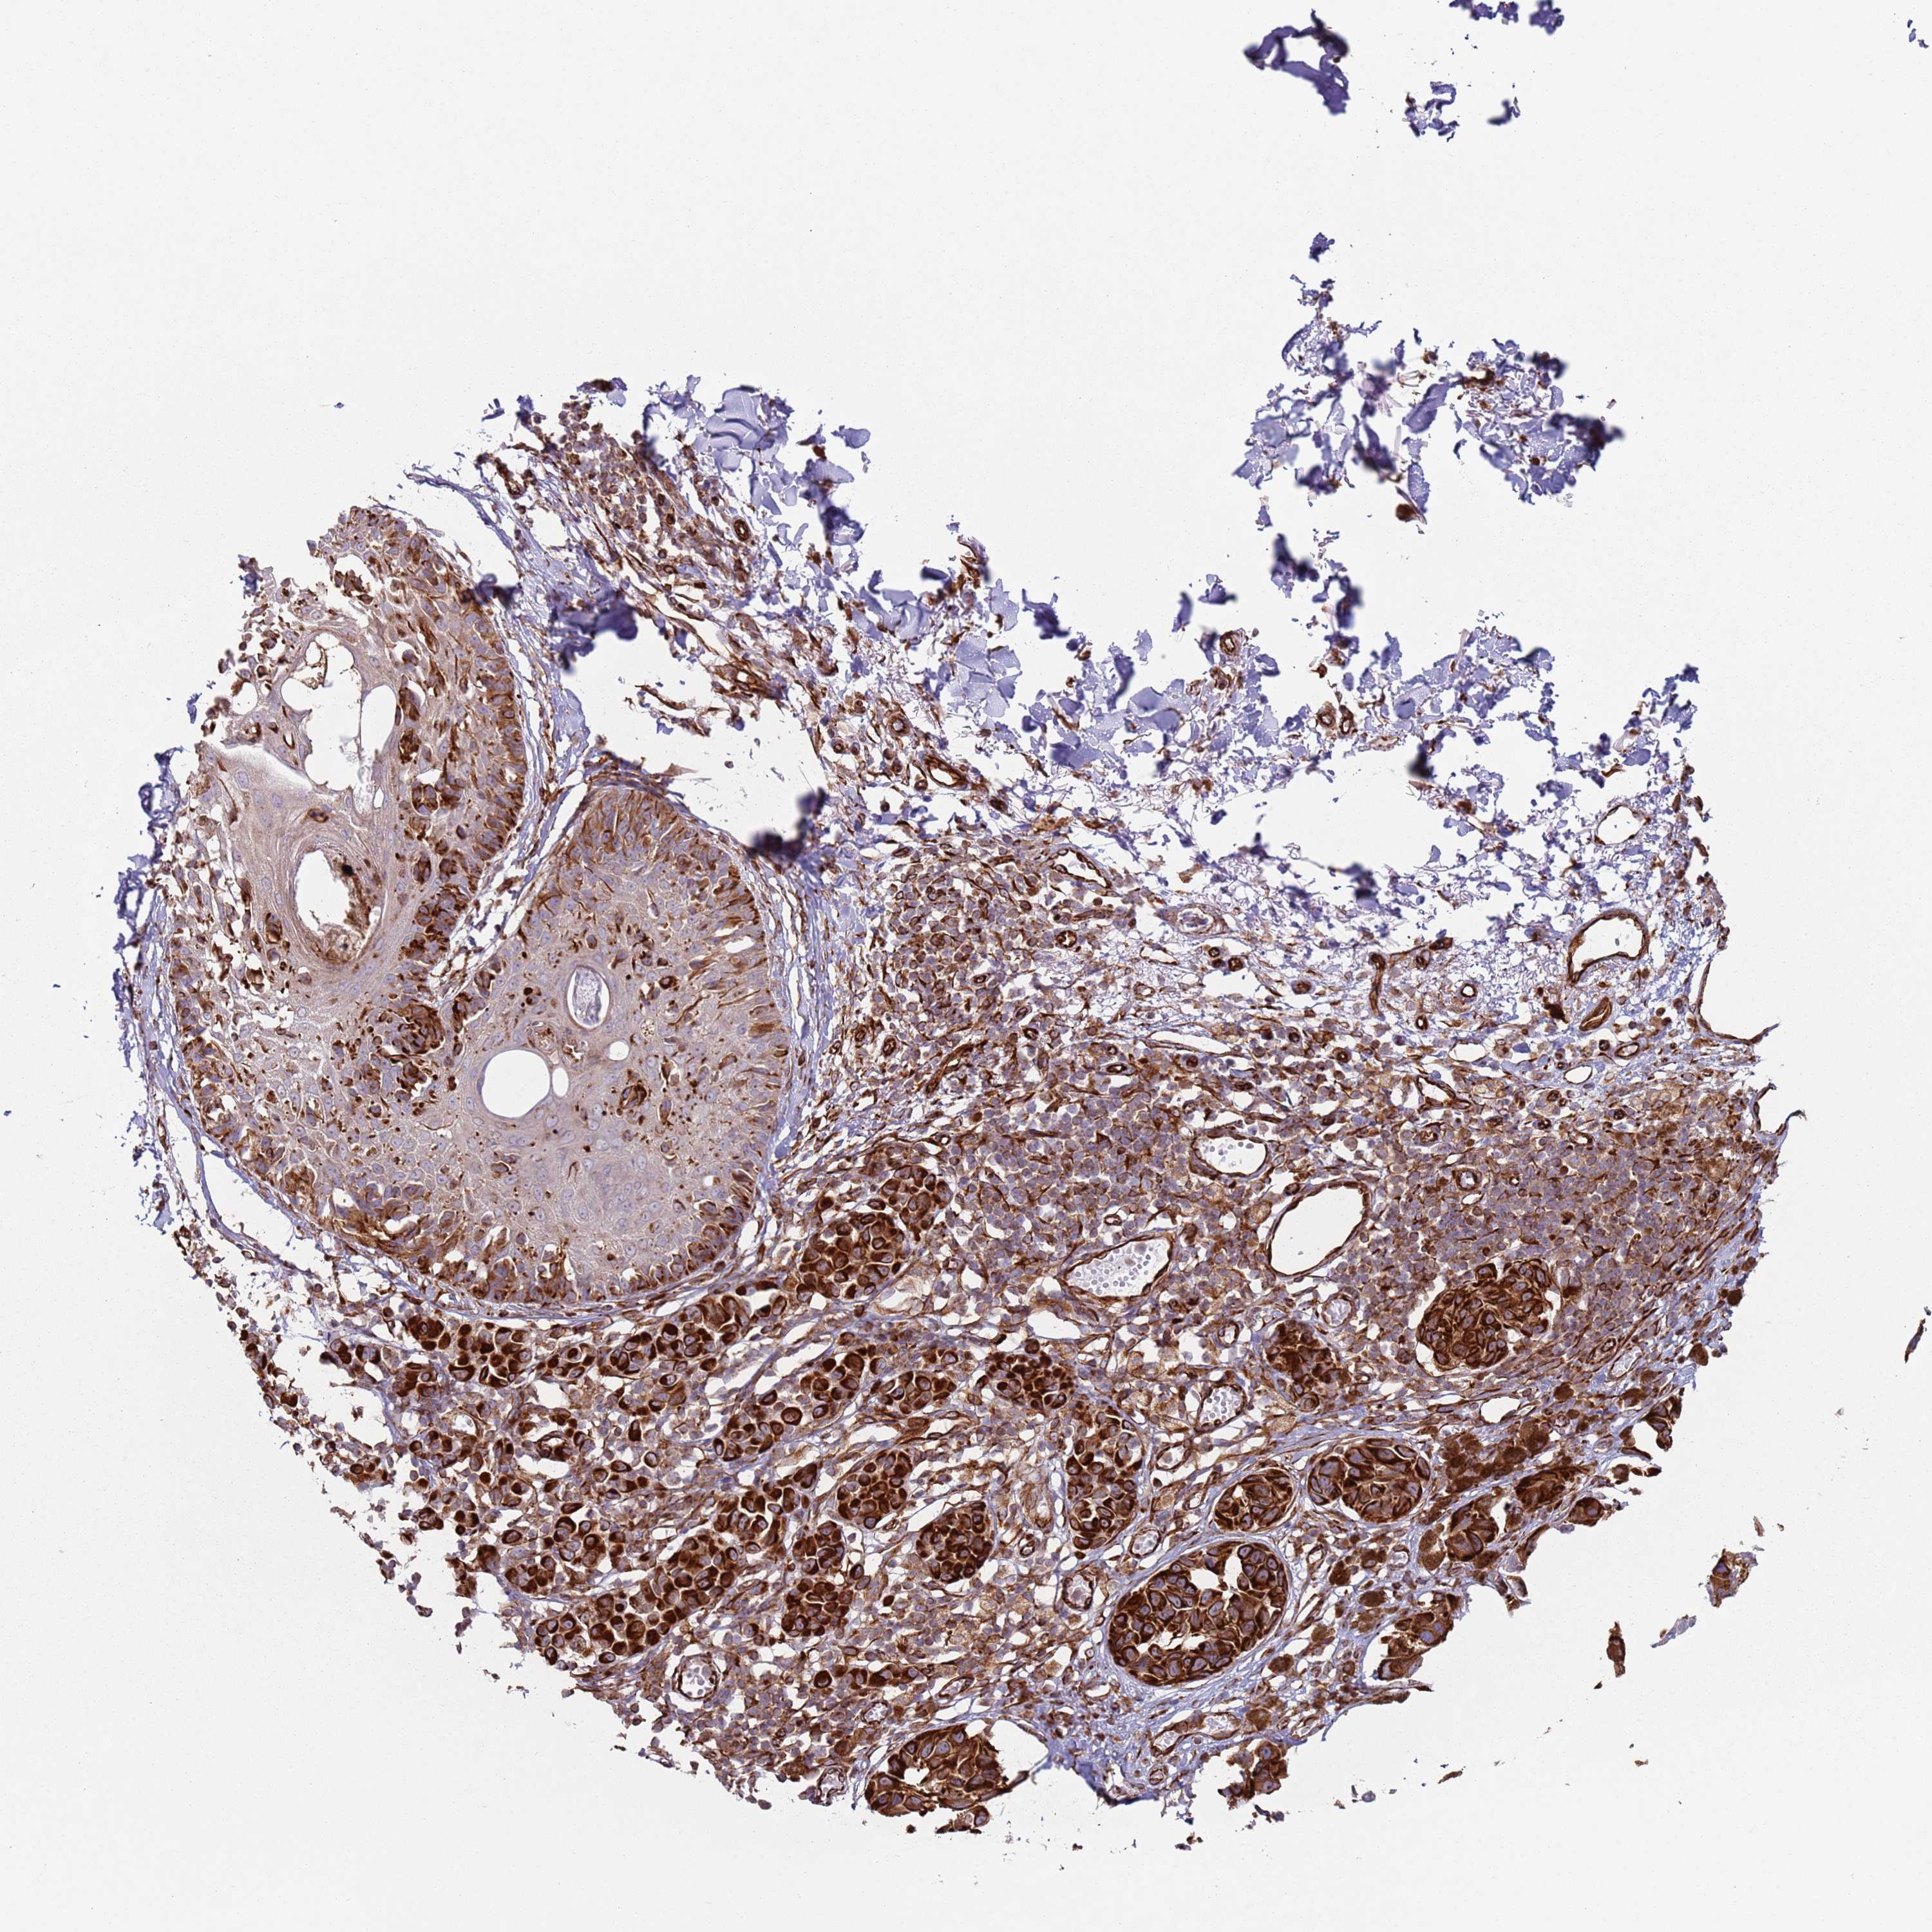

MELANOMA - Protein expressioni

A mouse-over function shows sample information and annotation data. Click on an image to view it in a full screen mode. Samples can be filtered based on level of antibody staining by selecting one or several of the following categories: high, medium, low and not detected. The assay and annotation is described here.

Note that samples used for immunohistochemistry by the Human Protein Atlas do not correspond to samples in the TCGA dataset.

Antibody stainingi

Antibody staining in the annotated cell types in the current human tissue is reported as not detected, low, medium, or high, based on conventional immunohistochemistry profiling in selected tissues. This score is based on the combination of the staining intensity and fraction of stained cells.

Each image is clickable and will lead to virtual microscopy that enables deeper exploration of all samples and also displays staining intensity scores, fraction scores and subcellular localization as well as patient and tissue information for each sample.

Antibody HPA046974

Staining

High

Medium

Low

Not detected

Intensity

Strong

Moderate

Weak

Negative

Quantity

>75%

75%-25%

<25%

None

Location

Nuclear

Cytoplasmic/membranous

Cytoplasmic/membranous,nuclear

Malignant melanoma, NOS

Malignant melanoma, Metastatic site